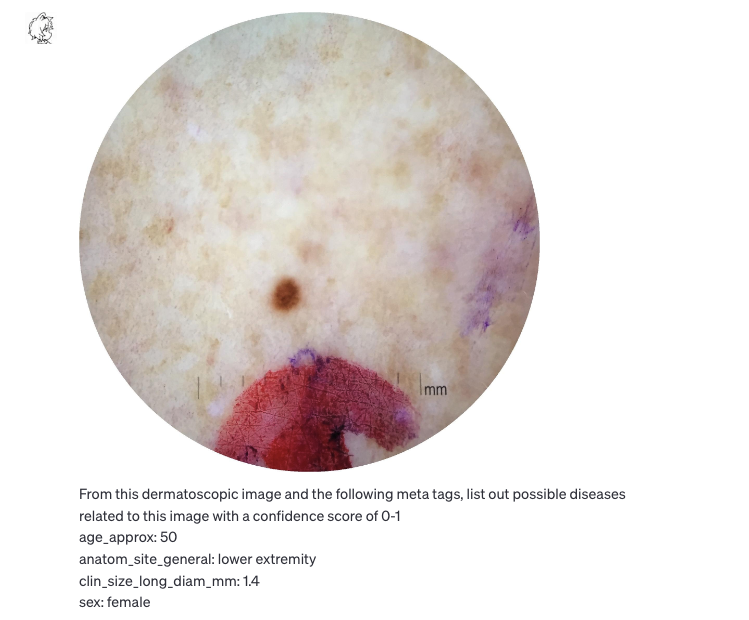

皮肤病:黑色素瘤判断(部分准确)

数据源:ISIC Archive

https://gallery.isic-archive.com/#!/topWithHeader/onlyHeaderTop/gallery?filter=%5B%5D

图片输入

GPT-V判别结果(常见痣 0.6,黑色素瘤 0.3)

- 黑色素细胞痣 (常见痣)

◦ 信心分数: 0.6

▪ 原因: 该皮损表现出与常见痣相似的特征,中央有深色区域。50岁左右的人群中很常见。

- 老年性角化病

◦ 信心分数: 0.4

▪ 原因: 老年性角化病是老年人中常见的非癌性皮肤生长,颜色可能会有所不同。

- 异型痣

◦ 信心分数: 0.5

▪ 原因: 这类痣与常见痣有所不同,通常较大。鉴于大小 (1.4mm) 和位置 (下肢),需要考虑此诊断。

- 黑色素瘤

◦ 信心分数: 0.3

▪ 原因: 黑色素瘤是一种皮肤癌,虽然所提供的图像有可能与黑色素瘤一致的特征,但需要皮肤科医生进行全面评估才能确诊。

- 基底细胞癌

◦ 信心分数: 0.2

▪ 原因: 它是最常见的皮肤癌形式,但所提供的图像没有基底细胞癌的典型迹象。但鉴于患者的年龄,仍需考虑。

- 血管瘤

◦ 信心分数: 0.2

▪ 原因: 血管瘤是由血管组成的良性肿瘤。图像中的红色可能暗示这一点,但从整体外观看,可能性较小。

上下文概念性工作,如文章头图的自动审核初筛、皮肤病的照片辅助筛选,DR/CT照片影像学诊断,提供HTML alt text等。